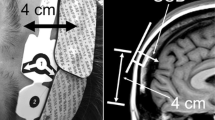

The major causes of cerebral ischemia are extensive hypoxic encephalopathy resulting from insufficient oxygen supply during arch branch reconstruction (cerebral hypoperfusion), and embolization resulting from atheromas dislodged from the atherosclerotic vessel wall. Techniques to protect the brain and thereby prevent intraoperative cerebral ischemia include DHCA, ACP, and RCP; the specific method used generally depends on the patient’s background factors and the policies of the surgical institution. The goal of DHCA is to protect the brain tissue by increasing its ischemic tolerance via hypothermia. However, since deep hypothermia (a nasopharyngeal temperature of 14–20 °C) allows for a cerebral ischemic time of 20–30 min [54, 55], DHCA alone is insufficient to ensure satisfactory cerebral protection during long surgeries. Therefore, ACP has emerged as an adjunct technique for brain protection, where an inflow cannula is inserted into the arch branch of interest. However, ACP carries a risk of releasing atheromas from the vessel wall during cannula manipulation. ACP may also cause cerebral ischemia if the cannula is malpositioned [56] (Fig. 1). By contrast, RCP provides brain perfusion via a superior vena cava cannula, i.e., in the reverse direction of normal blood flow. In a retrospective analysis of 1193 patients who underwent DHCA for the treatment of aneurysms involving the ascending aorta and arch, the rate of cerebral infarction was 1.7% with RCP and 30% without RCP in patients whose circulatory arrest time exceeded 40 min [57]. These results showed that RCP extended the cerebral ischemic time. However, retrograde perfusion is not a physiologically normal method of circulation, and it may cause brain edema [58]. It is often recommended that the retrograde superior vena cava perfusion flow rate be set below 400 mL/min and that venous pressure be maintained between 15 and 25 mmHg [59].

Catheter malposition was detected in 4 (11.4%) of 35 consecutive patients with aortic arch aneurysm undergoing total arch replacement (n = 13) or transaortic stent graft implantation (n = 22) [56]. Catheter malposition can prevent blood flow to the right common carotid artery (arranged form the figure in the article [56])